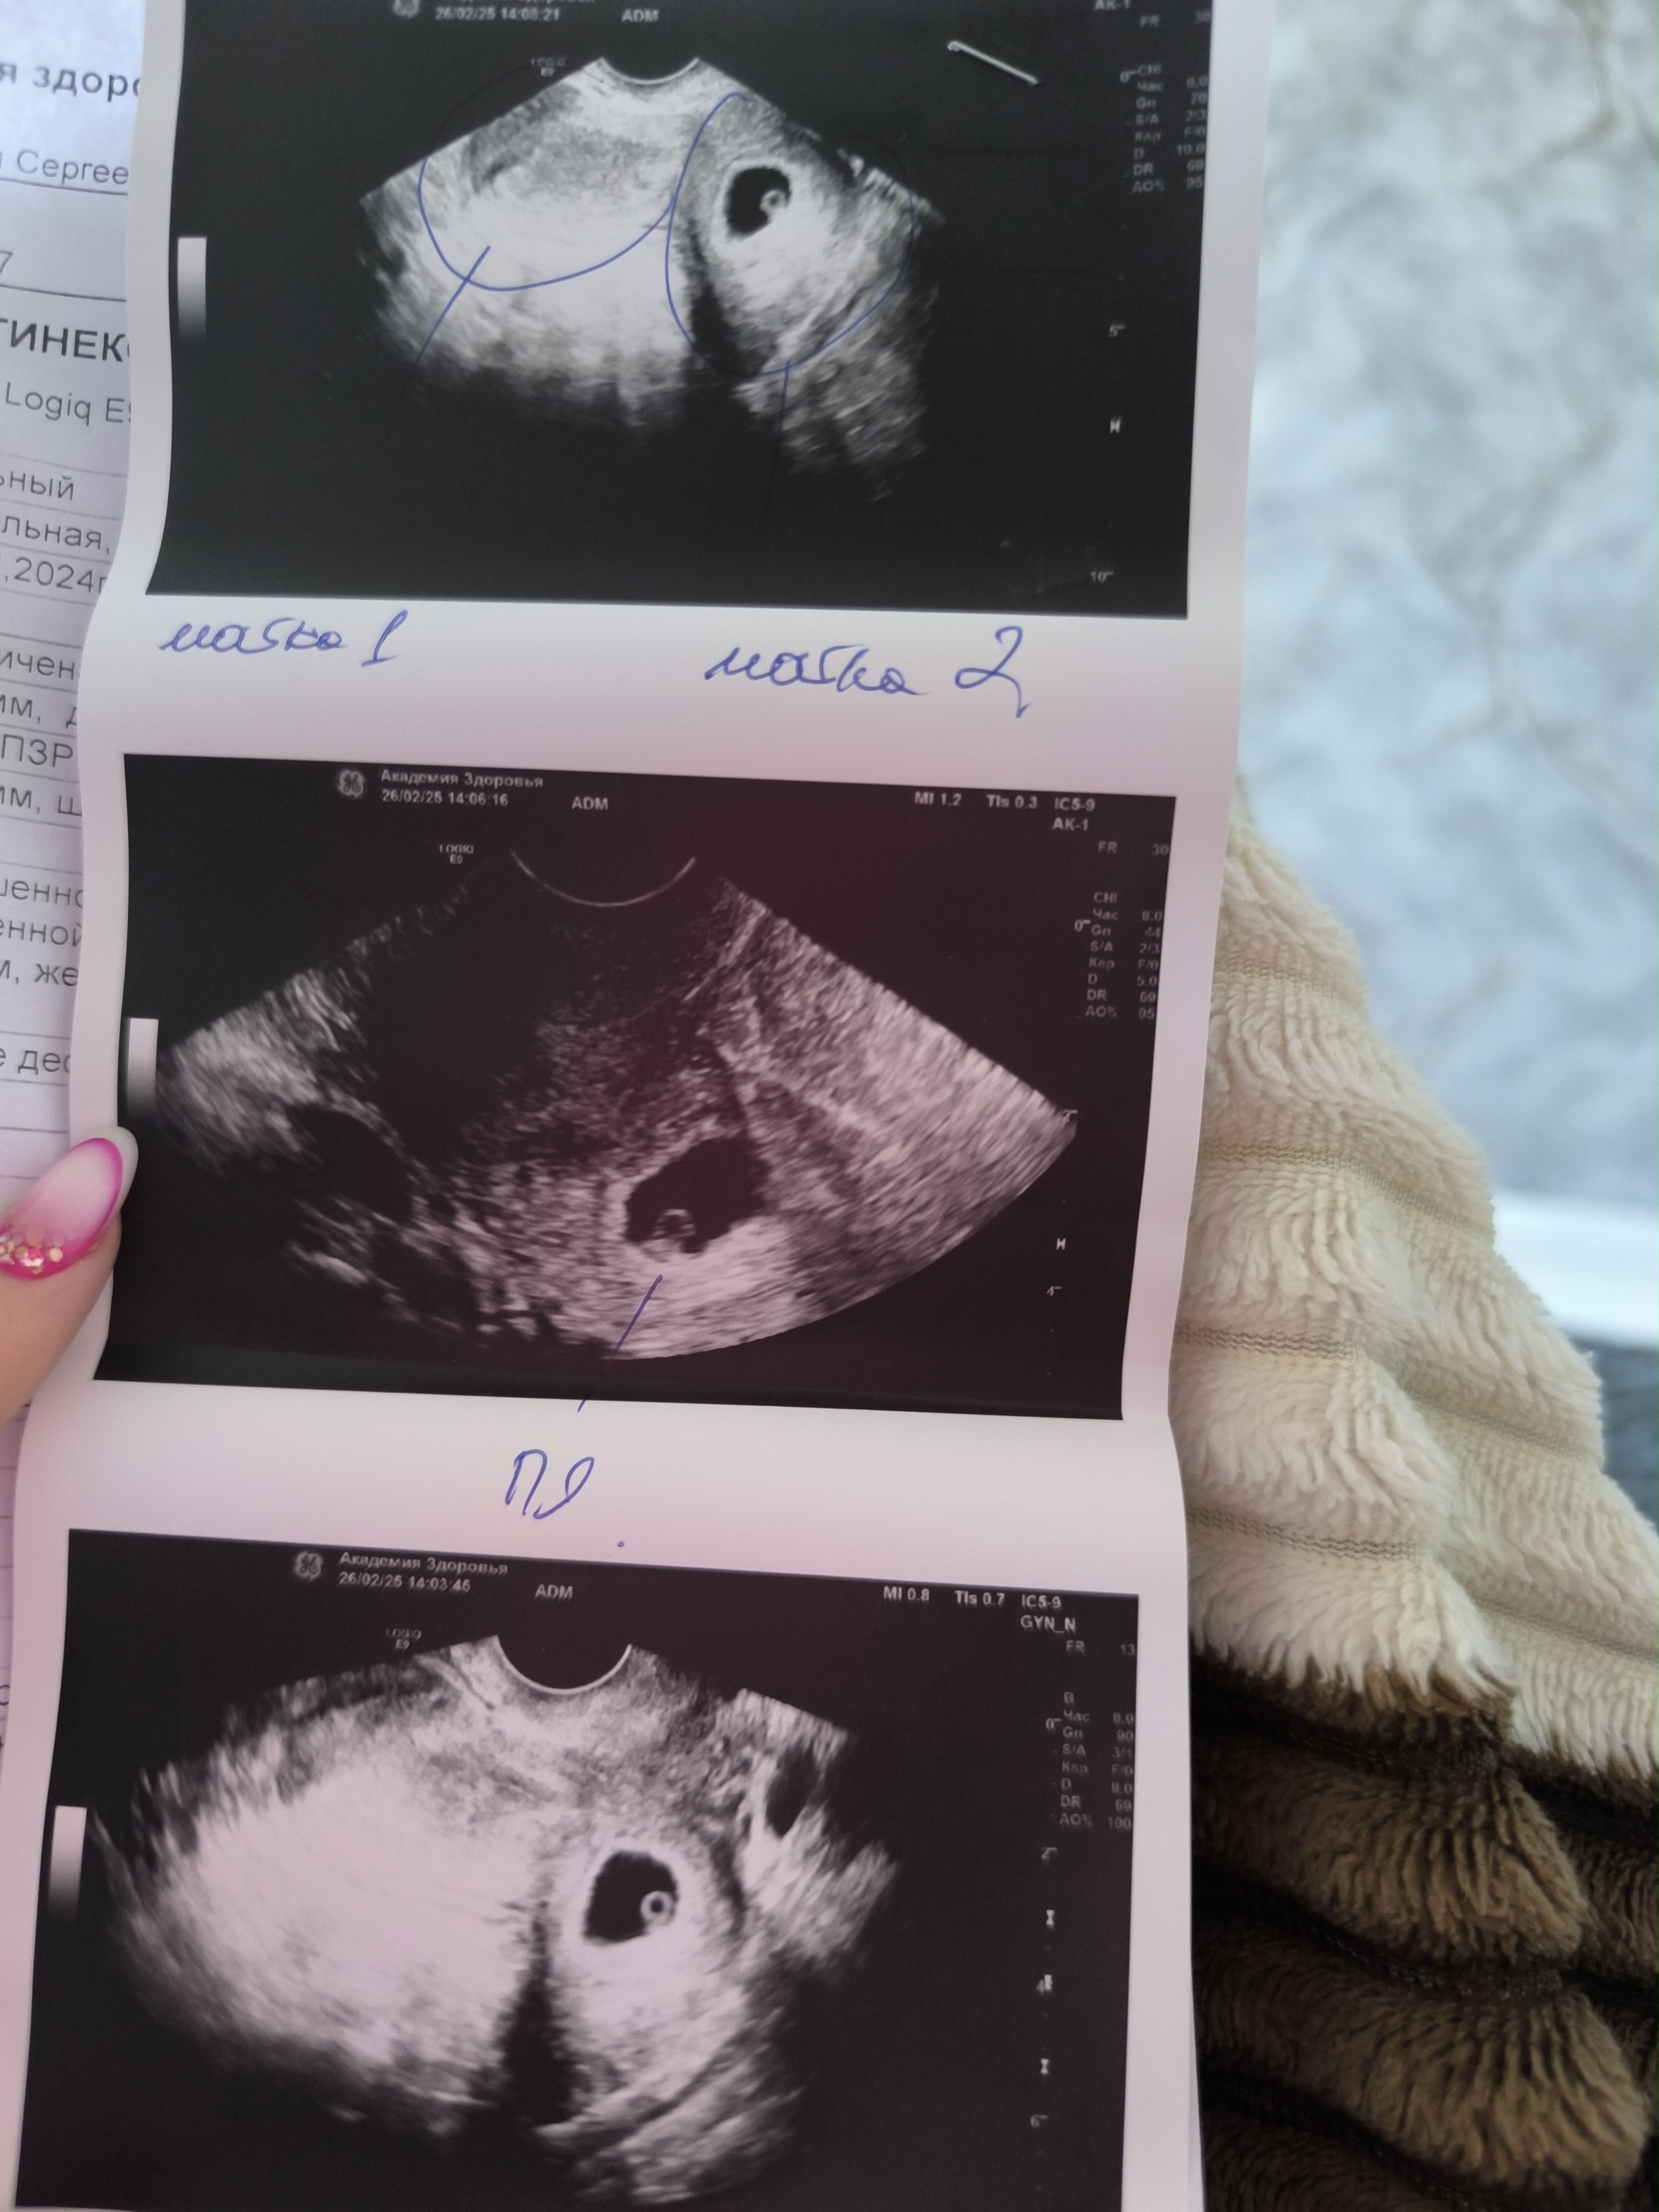

А что значит матка 1 и матка 2?😂

Все ок,срок 6 недель,но у меня вопрос про две матки не снят

Маруся, удвоенная матка. Особенность строение есть такая у некоторых женщин

Анастасия , особенность строения или прям 2 штуки?

Глянула,двурогая называется,такое знала